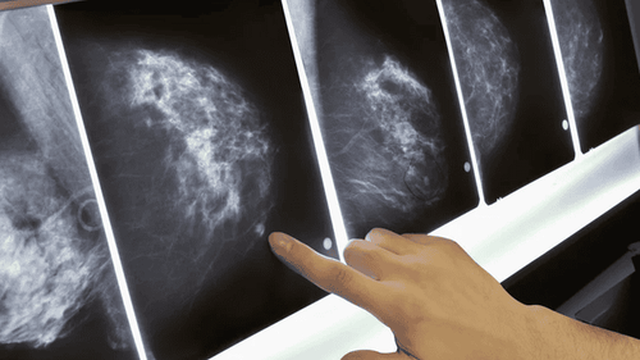

Nhũ ảnh là phương pháp duy nhất phát hiện được vi vôi hóa, dấu hiệu sớm nhất của ung thư vú giai đoạn 0. (Ảnh minh họa: Internet)

Đây là chìa khóa quan trọng nhất. Nhũ ảnh là phương pháp duy nhất phát hiện được vi vôi hóa, dấu hiệu sớm nhất của ung thư vú giai đoạn 0. Từ 40 tuổi trở lên, chị em nên chụp mỗi năm một lần. Nếu có mẹ, chị gái từng mắc ung thư vú, nên bắt đầu từ 35 tuổi. "Đây chính là lý do giúp bệnh nhân của mình phát hiện bệnh khi còn cực kỳ sớm", BS Tuấn nhấn mạnh.